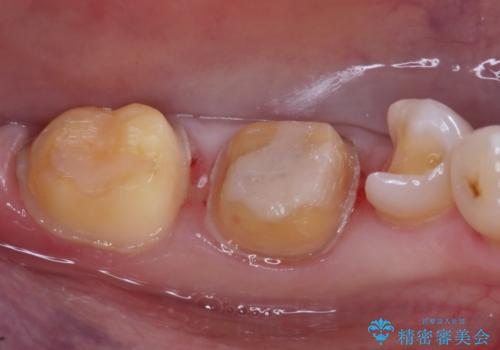

- ご友人との会話中などに、下の歯に入れてあるメタルインレーが見えてしまうのが気になり、やり変えを希望された患者様です。審美性、清掃性に優れたセラミックでの治療を希望されたため、セラミックインレー、クラウンで治療いたしました。